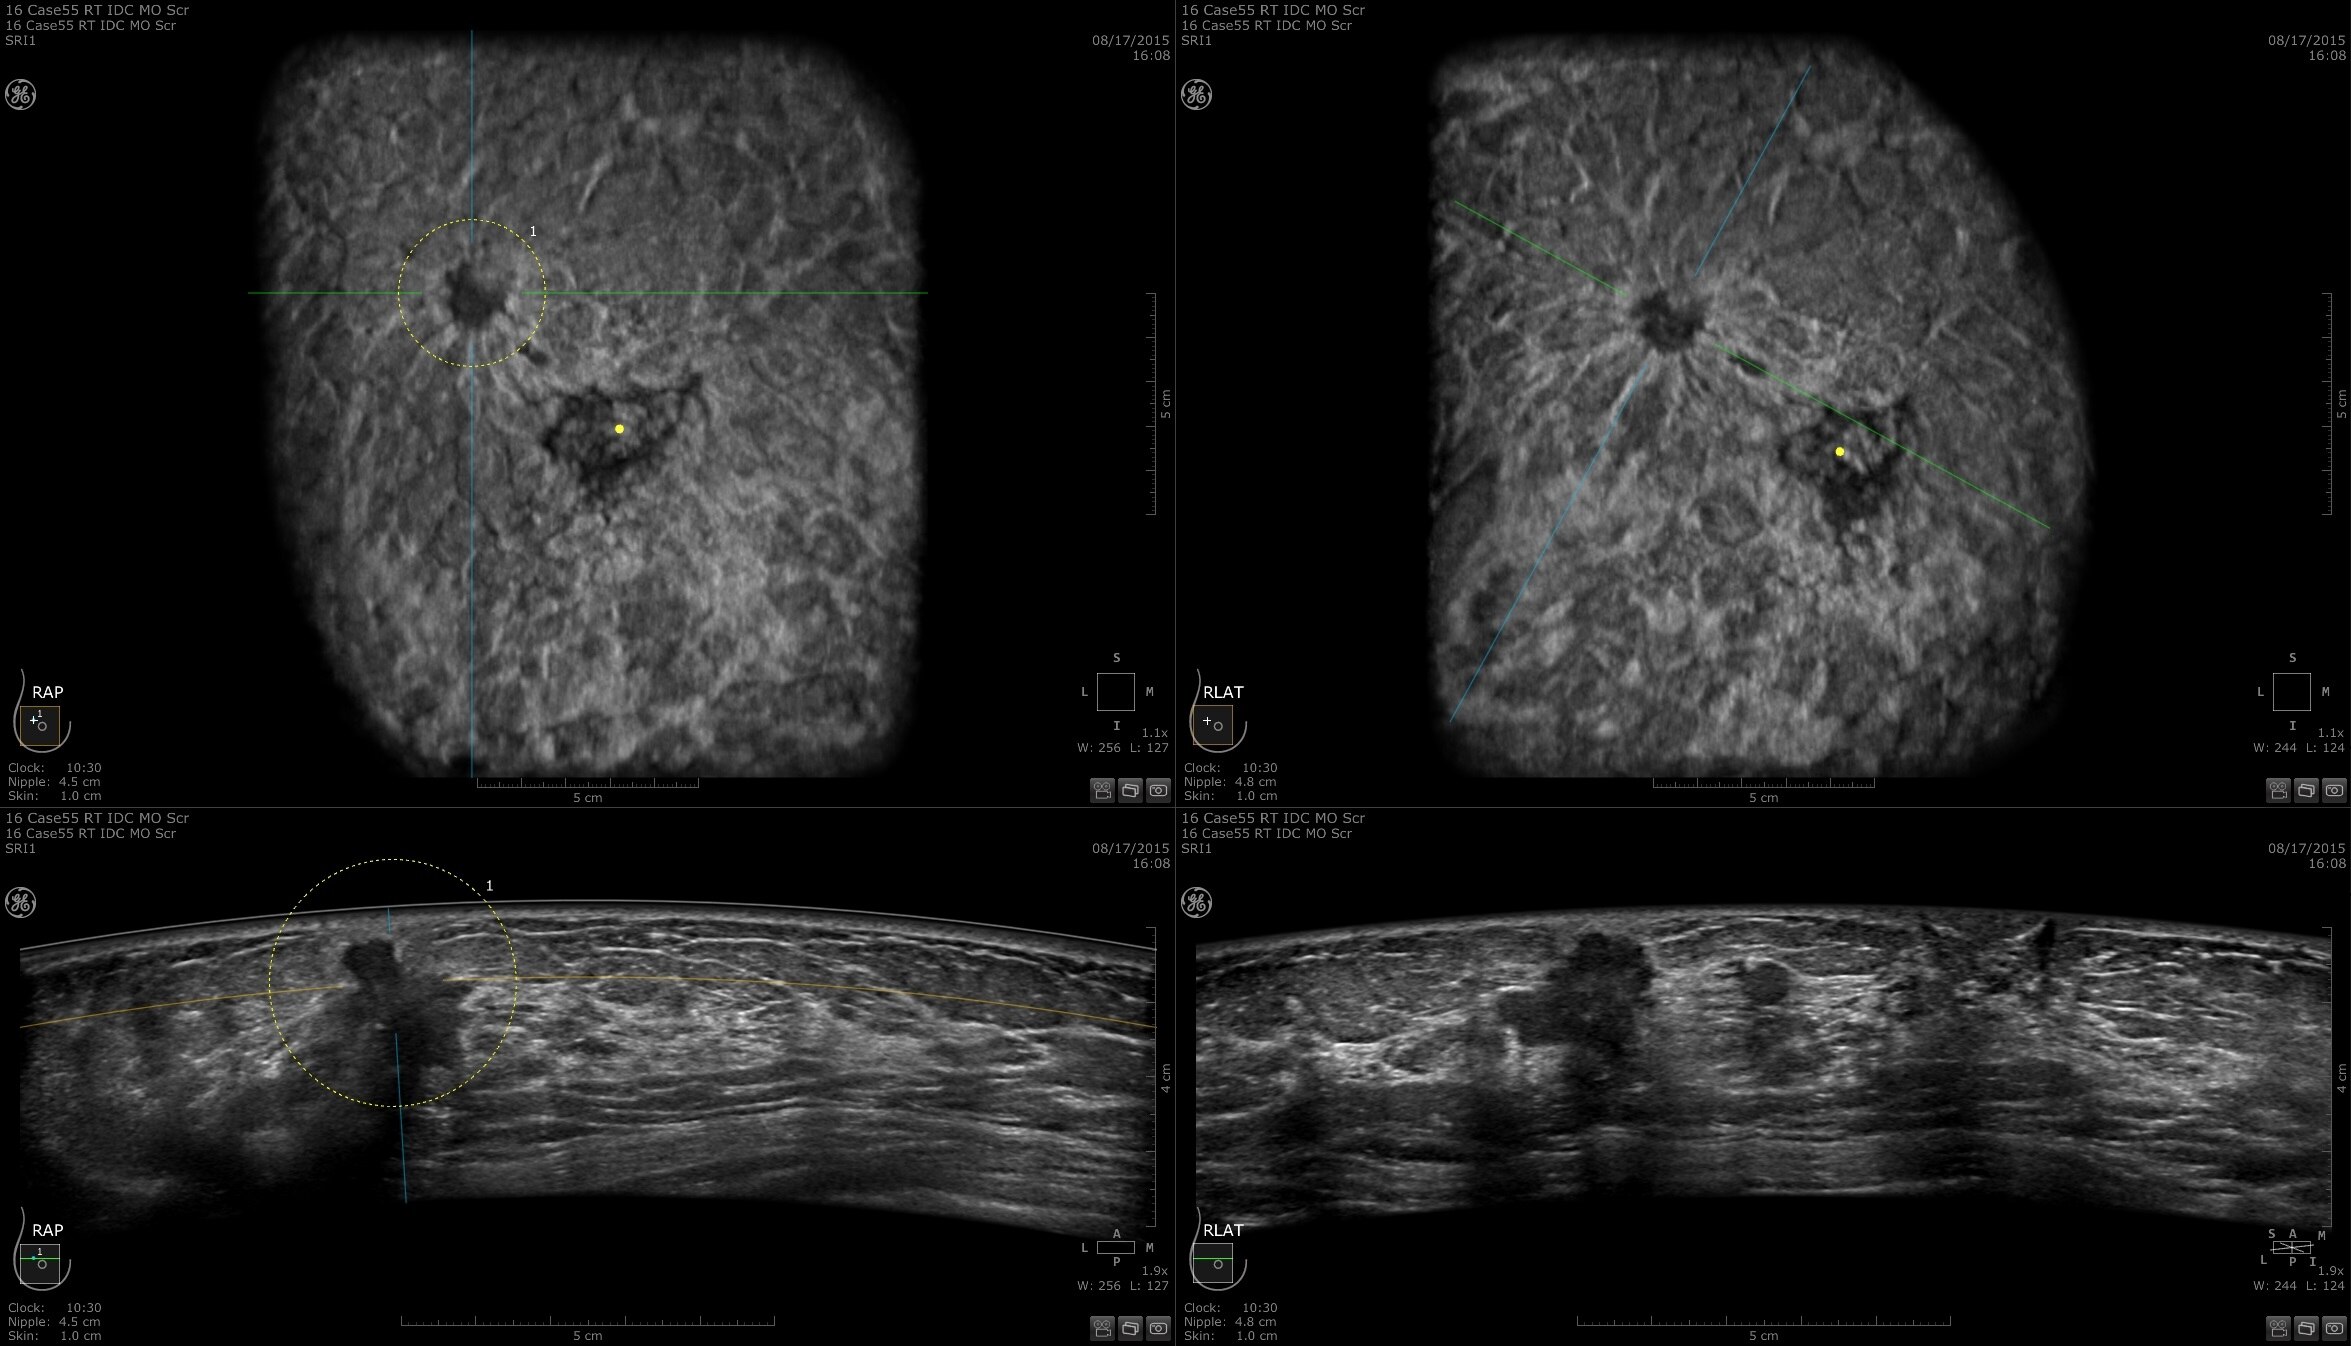

Dense breast tissue and cancer appear white on a mammogram, potentially camouflaging small cancers. Invenia ABUS 2.0, is specifically designed to help clinicians find cancers that may be hidden on mammography1,2.

Lesion characterization for confident staging in dense breasts

Invenia ABUS 2.0 uses the latest ultrasound innovations and AI based solutions to help improve precise diagnosis and elevate clinical confidence.